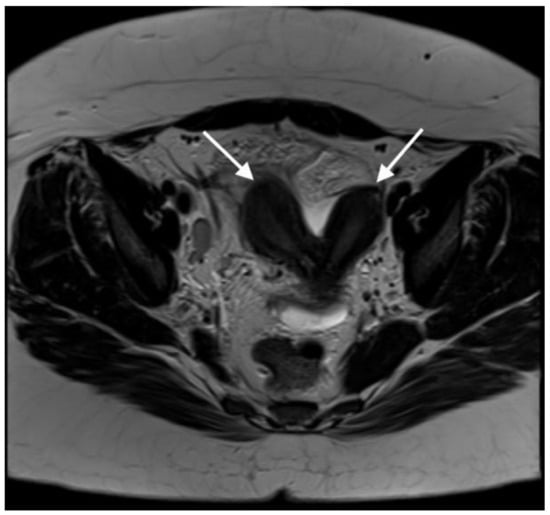

Sagittal T2-weighted MR image showing a vaginal septum with a haematopyocolpos of the obstructed hemivagina and a tubo-ovarian abscess (red arrow indicates the obstructed haematopyocolpos, and white arrow shows the tubo-ovarian abscess). The presence of gas and fluid within the lumen was indicative of a concurrent infection. The patient was initially treated with intravenous antibiotics after the provisional diagnosis of PID. After three days of treatment, she continued to have episodes of pyrexia, the CRP level remained high (242 mg/L) and there were persistently high WCC (16.5 × 109/L) and platelet quantities (500 × 109/L). On the third day after admission, the diagnosis of OHVIRA syndrome was finalised, and the decision was taken to take the patient for surgical intervention to drain the haematocolpos and perform a laparoscopic exploration, to which the patient consented. The next day, the patient underwent an examination under anaesthesia, vaginal septectomy and drainage of the haematopyocolpos. Intraoperative hysteroscopy confirmed the presence of a uterus didelphys bicollis. The cervix of the affected cavity was dilated to encourage continuous drainage. Subsequently, during the laparoscopy, significant pelvic adhesions were noted, involving the bowel being adherent to the uterus, and a large right-sided tubo-ovarian abscess. Laparoscopic adhesiolysis was performed, as well as the drainage of the abscess. The pelvic drain was left in situ at the end of the procedure. She remained an inpatient for four days after surgery. The drain was removed three days after the operation. She was continued on intravenous antibiotics for a further three days before they were converted to oral medication. She no longer had a post-operative spiking temperature, and her pulse normalised two days after the operation. Her CRP dropped to 51 mg/L and WCC to 9.5 × 109/L on the day of discharge. She was followed up in the Gynaecology Clinic with repeat imaging that confirmed the resolution of the tubo-ovarian abscess. She was carefully debriefed about the implications of having uterus didelphys and a single kidney in pregnancy and was further signposted to written information provided by the British Society of Paediatric and Adolescent Gynaecology.

Coronal T2-weighted MR image shows 2 cervical canals (White arrow indicates the two cervical canals. The right-sided cervix leads to the obstructed haematopyocolpos). OHVIRA syndrome, also known as Herlyn–Werner–Wunderlich syndrome, is a rare uterine and renal congenital abnormality which is characterized by an obstructed hemivagina and ipsilateral renal agenesis [2]. The exact prevalence of the syndrome has not been yet estimated, but it has been reported that it accounts for 0.16–10% of Mullerian abnormalities, the incidence of which is 2–3% of the population [3]. Assessment via pelvic ultrasound in combination with MRI helps to establish an accurate clinical diagnosis [4]. In the majority of cases, pubertal women are more likely to be identified with the syndrome, since the onset of menstrual periods might lead to hematometra and/or delayed menarche. However, in cases of partial obstruction, the diagnosis can be elusive, often taking years to be established, leading, at times, to women presenting in adulthood with symptoms resembling pelvic infection and endometriosis [2]. Septectomy remains the treatment of choice and should be performed in all affected patients. Knowledge of this rare condition and maintaining high levels of suspicion is critical in these cases [5,6].